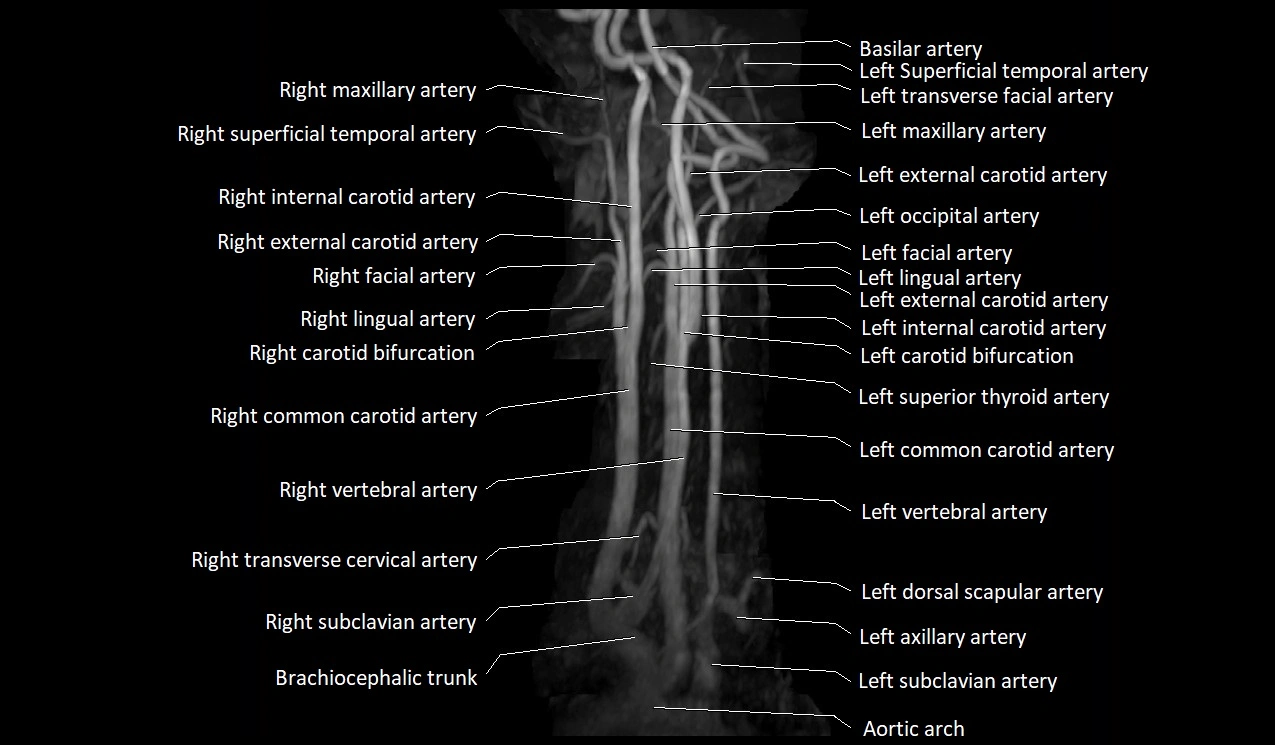

CT image

image